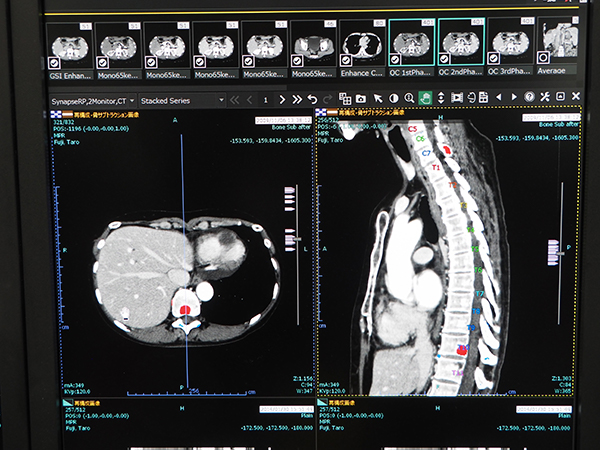

ITソリューションでの最大の目玉となったのが,4月4日にリリースされたAIプラットフォーム「SYNAPSE SAI viewer」である。富士フイルムが開発を進めてきたメディカルAI技術「REiLI」の最初の製品であり,“画像診断ワークステーション用プログラム”で薬機法の認証を受けた製品として2019年7月に発売の予定だ。SYNAPSE SAI viewerでは,ディープラーニングを用いて開発された機能として,“臓器セグメンテーションおよびラベリング”,“骨経時サブトラクション”,“Virtual Thin Slice”が提供される。そのほか,読影ビューワとしての基本機能を持ち,3D画像の表示機能も搭載されている。骨経時サブトラクション機能では,椎骨一つ一つを認識した上で過去画像との位置合わせを行い,サブトラクションを行ってCT値の経時的変化を算出して骨転移の診断をサポートする。Virtual Thin Sliceでは,thickスライスで撮影されたCTデータからthinスライスの画像を仮想的に生成して,同じ条件での読影を可能にする。

AIプラットフォーム「SYNAPSE SAI viewer」の“骨経時サブトラクション機能”